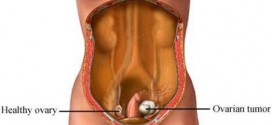

El arrenoblastoma. Recordemos que la Trofología avanzada (binipatia), tiene el extraordinario poder de eliminación de las células cancerígenas (tumores), al igual que su maravillosa estrategia para detener el cáncer, al provocar la muerte de las células del cáncer por hambre. Esta es la maravillosa estrategia de la Trofología avanzada, hacer morir de hambre al cáncer mientras alimenta a las células …